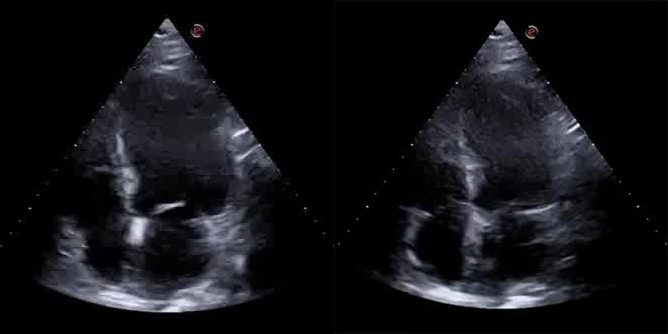

A bedside cardiac ultrasound was then performed, which showed evidence of akinesia in the apex and periapical segments, the mid anteroseptal segment, and the anterior wall, and hypokinesia in the mid anterolateral segment, leading to a mild decrease in overall systolic function (left ventricular ejection fraction [LVEF]: 43%). The left ventricle was slightly dilated with a minor increase in parietal thickness and a II degree diastolic dysfunction. Additionally, there was mild enlargement of the left atrium, mild-to-moderate mitral regurgitation, and mild tricuspid insufficiency with an estimated pulmonary arterial pressure systolic (PAPs) of 45 mmHg (Fig. 3).

Fig. 3.

Fig. 3.End-diastolic frame (Left) and End-systolic frame (Right) of the bedside cardiac ultrasound showing evidence of hypo-akinesia in the apex, periapical segments, mid anteroseptal segment and the anterior wall, leading to a mild decrease in overall systolic function (left ventricular ejection fraction [LVEF]: 43%).

The Cardiac Intensive Care Unit (CICU) was promptly notified, and the transfer was arranged accordingly. In the meantime, an additional hs-troponin test was performed, and a bedside echocardiogram was carried out, which confirmed the akinesia in the apex and in the septal segments. These myocardial territories are supplied by the left anterior coronary artery, thus further corroborating the diagnosis.

Echocardiographic examination revealed a mildly dilated left ventricle with normal parietal thickness. Akinesia in the apex, periapical segments, middle septum, and middle anterior wall was also noted. Additionally, there was a moderately depressed global systolic function, with an ejection fraction of 40%. The exam also showed moderate mitral valve insufficiency.